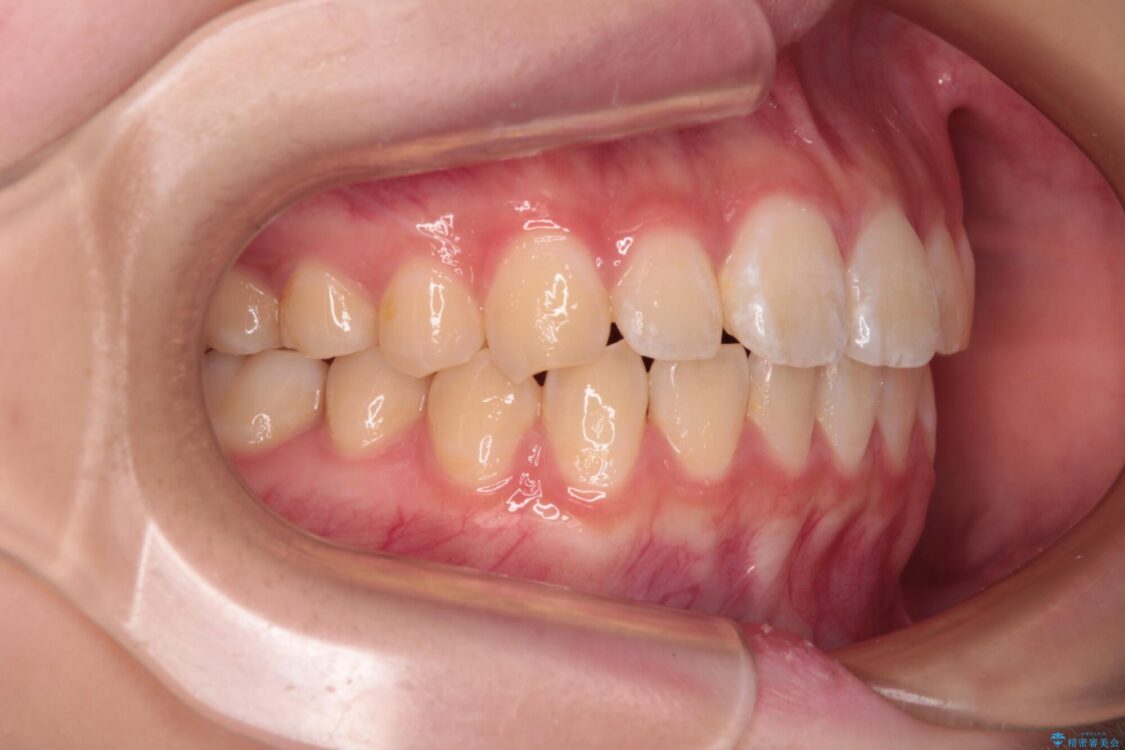

治療途中

• インビザラインは使える自信がない ワイヤー装置にて矯正治療 治療途中画像